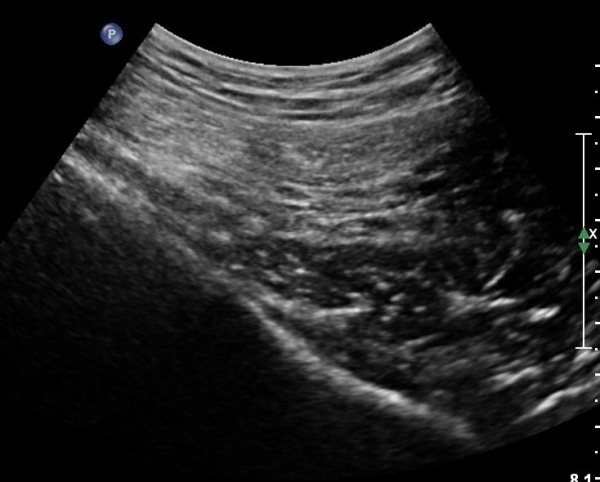

ÈÄ»óÀå°ñ±Ø ¿ÜÃø¿¡ ŽÃÊÀÚ¸¦ ¼öÆòÀ¸·Î ´ë¸é ½ÉÃþÀ¸·Î Àå°ñÀÌ °üÂûµÇ°í Àå°ñ Ç¥Ãþ¿¡ ´ëµÐ±Ù°ú ÁߵбÙÀÌ °üÂûµÈ´Ù(»çÁø 1).